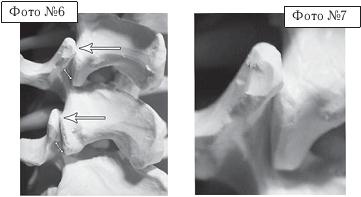

На фото № 6 макета позвоночника наблюдается смещение (подвывих) суставных поверхностей дугоотростчатых суставов. На фото № 7 наблюдается смещение (подвывих) суставных поверхностей дугоотростчатого сустава (увеличенный вариант). ![]() На фото № 8 макета позвоночника наблюдается перерастяжение дугоотростчатых суставов вследствие вытяжения. На фото № 9 наблюдается перерастяжение дугоотростчатого сустава (увеличенный вариант). ![]() Фото № 10 На фото № 10 макета позвоночника наблюдается нормальное взаимоотношение суставных поверхностей дугоотростчатых суставов, в норме высота межпозвонкового диска и межпозвонковых отверстий. ![]() Фото № 11 На фото № 11 макета позвоночника наблюдается смещение (подвывих) суставных поверхностей дугоотростчатых суставов. Подобное смещение, как правило, происходит вследствие развития дегенеративно-дистрофических процессов в межпозвонковом диске. При этом уменьшается высота диска, сужается просвет фораминального отверстия (межпозвонкового), что может способствовать ущемлению спинномозговых корешков (нервов) и сосудов. ![]() Фото № 12 На фото № 12 макета позвоночника наблюдается перерастяжение дугоотростчатого сустава вследствие вытяжения, расширение фораминального отверстия, а также растяжение задних отделов фиброзного кольца межпозвонкового диска и сближение вентральных (передних) отделов тел позвонков. Это приводит межпозвонковый диск в клиновидное состояние, что способствует выталкиванию содержимого межпозвонкового диска из передних его отделов в задние. |